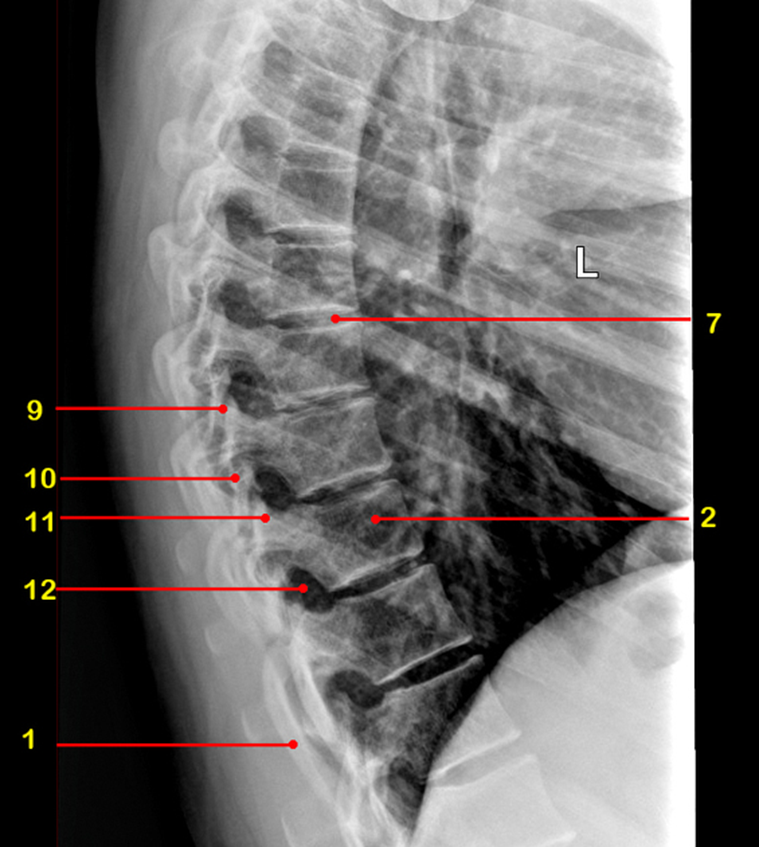

What is 1

rib

What is 2

vertebral body

What is 7

intervertebral disc

What view is this

AP

What is 9

facet joint

What is 10

inferior articular process

What is 11

superior articular process

What is 12

intervertebral foramen

sagittal